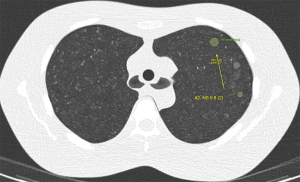

In digital two-dimensional (2D) images, a pixel is the smallest addressable element. Although it occupies a certain area in the image, it is treated as a dot, which theoretically does not have an area. The Euclidean distance between two distant pixels in an image is calculated using the coordinates of the center of two pixels (Figure 1). To obtain the physical distance between two points, the Euclidean distance is multiplied by the pixel spacing (the physical distance between the centers of neighboring pixels). In a virtual three-dimensional (3D) space made of 2D radiological images, a voxel (a virtual volumetric unit which is a cuboid having a pixel as the floor) is the smallest addressable element. The physical volume of a voxel is a square with one pixel spacing as the floor and a height of the slice interval (interslice distance). The Euclidean distance between two voxels is calculated as in the 2D image, using the coordinates of the center of two voxels.